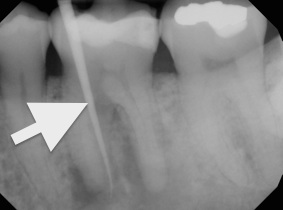

5. Current radiographic examination.

Chronic apical abscess is typically indicated by a radiograph that reveals a radiolucency. Clinically, there is a sinus tract present on the gingival tissue. It is paramount that the draining sinus tract be traced with a gutta-percha cone and then radiographed (Figure 3 and Figure 4).

Radiographic confirmation of periradicular diagnosis—chronic apical on tooth No. 19. Note the tracing of the inserted gutta-percha to the etiology. Local anesthesia is generally not required for a sinus tract tracing.

Figure 4